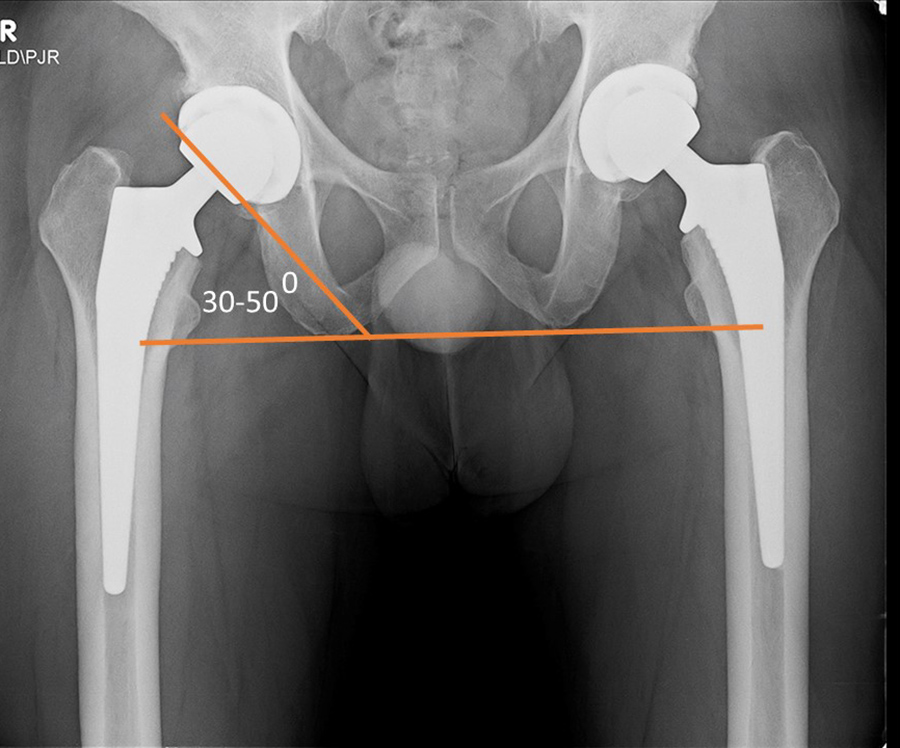

Radiography is essential for the evaluation of hip arthroplasty. A standard AP view of the pelvis and a cross-table lateral view of the pelvis are usually recommended (Jacobson, 2015). A standing AP pevic radiograph is often also included. The preferred position for the acetabular cup is 40°–50° of abduction

from the horizontal plane and 20° anteversion

from the coronal plane (figures: hip arthroplasty evaluation). The prosthetic femoral head is evaluated for its vertical and horizontal positions relative to the contralateral normal hip, when present, in a number of ways (Manaster, 1996; Mulcahy, 2012; Jacobson, 2015; Deshmukh, 2019). One method for evaluating the vertical position of the femoral head is to draw a line (A) tangential to the ischial tuberosities, a line (B) tangential to the tops of the greater tuberosities, and a line (C) through the centers of the femoral heads whether a prosthetic femoral head or a native femoral head. Ideally, these lines should be parallel. To evaluate the horizontal position of the femoral head the distances between the femoral heads and the tops of the acetabular tear drops on each side are measured. Ideally, these distances should be equal.

| Bilateral total hip arthroplasty (THA) |

| 38 year old man with bilateral THA for advanced osteoarthritis. The acetabular cup on an AP view of the pelvis should have 30-50 degrees of lateral inclination, which is measured as the angle between the rim of the acetabular cup and a line tangential to the ischial tuberosities. |